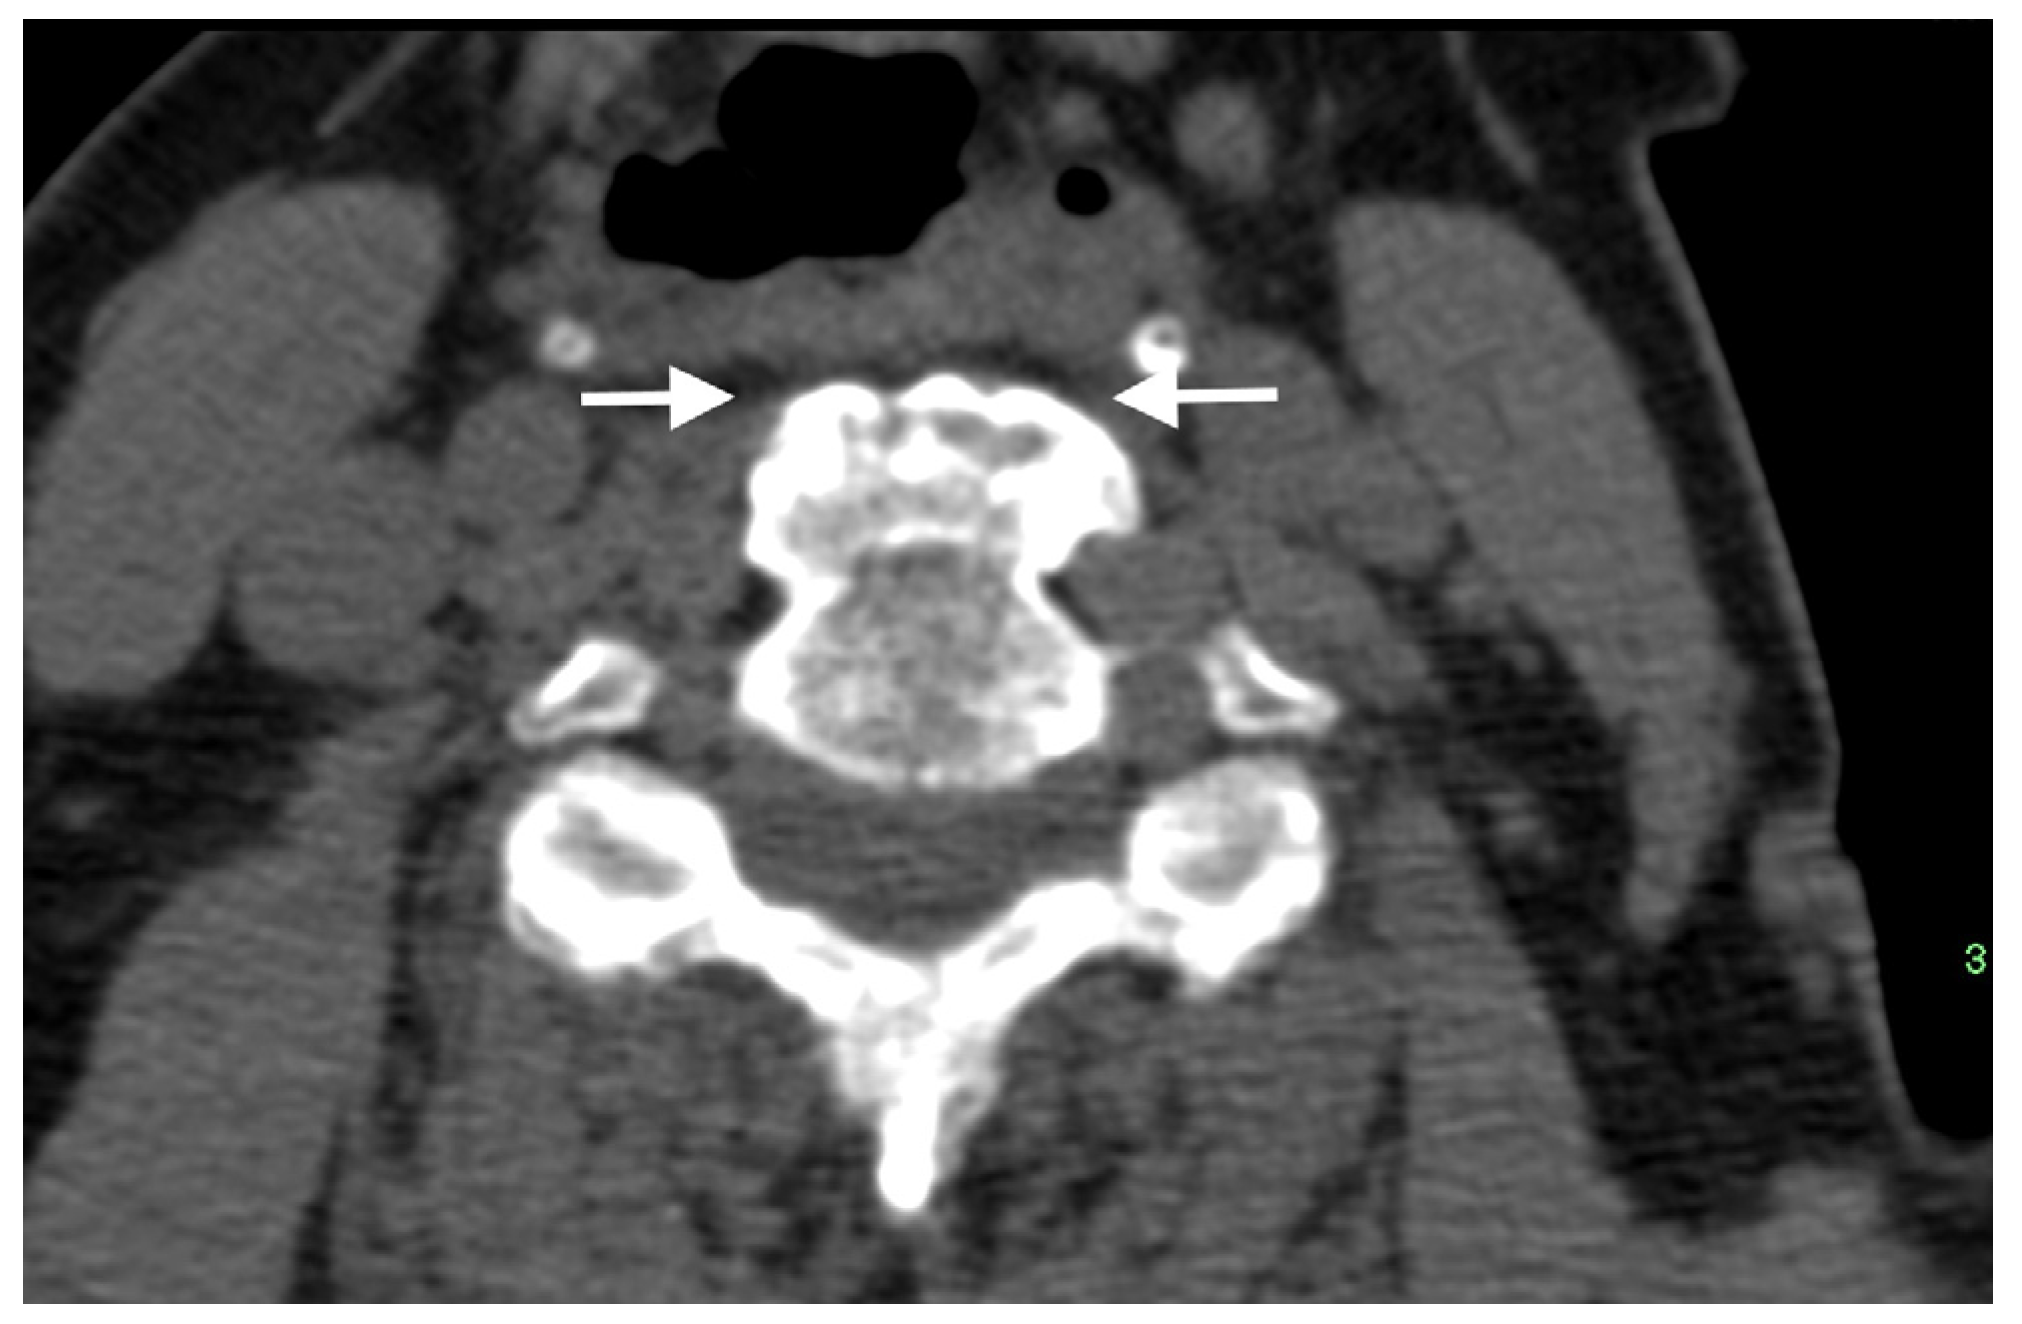

To distinguish between SpA and DISH, the SIJs appear as an exclusion criterion in the Resnick and Niwayama criteria, so that findings compatible with sacroiliitis, such as erosions, sclerosis, and ankylosis of the SIJ on pelvic radiographs, preclude the diagnosis of DISH [1]. In subsequent studies, Resnick and co-workers described the presence of SIJ osteophytes, para-articular bony bridging, and coexisting osteoarthritis on pelvic radiographs of subjects with DISH [4,66]. Over time and with advances in imaging technology, the characterization of SIJ involvement in DISH has been refined for both CT and MRI. Extra-articular bridging osteophytes located ventrally to the SIJs, similar to flowing osteophytes in the spine, are commonly seen in DISH patients, resulting from enthesopathy of the involved ligament (Figure 7A) [67,68]. This anterior SIJ bridging overlying the SIJ on pelvic radiographs obliterates the joints, resulting in a false diagnosis of SIJ ankylosis, and thus SpA [67,69]. Indeed, studies evaluating the SIJs of subjects with DISH on CT have shown that anterior bridging of the SIJ is a common finding [70,71], but in contrast with the Resnick and Niwayama criteria, both intra-articular and posterior entheseal ankylosis are also prevalent in DISH (Figure 7B) [70,71].

Figure 7.

Axial CT images of the SIJs of two patients with DISH. (A) Characteristic extra-articular bridging osteophytes are seen anterior to the SIJs. (B) In addition to the ventral extra-articular osteophytes, clear ankylosis can be observed within the right and left SIJs.